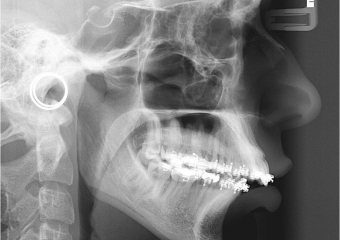

Telerradiografia inicial

Telerradiografia após a cirurgia